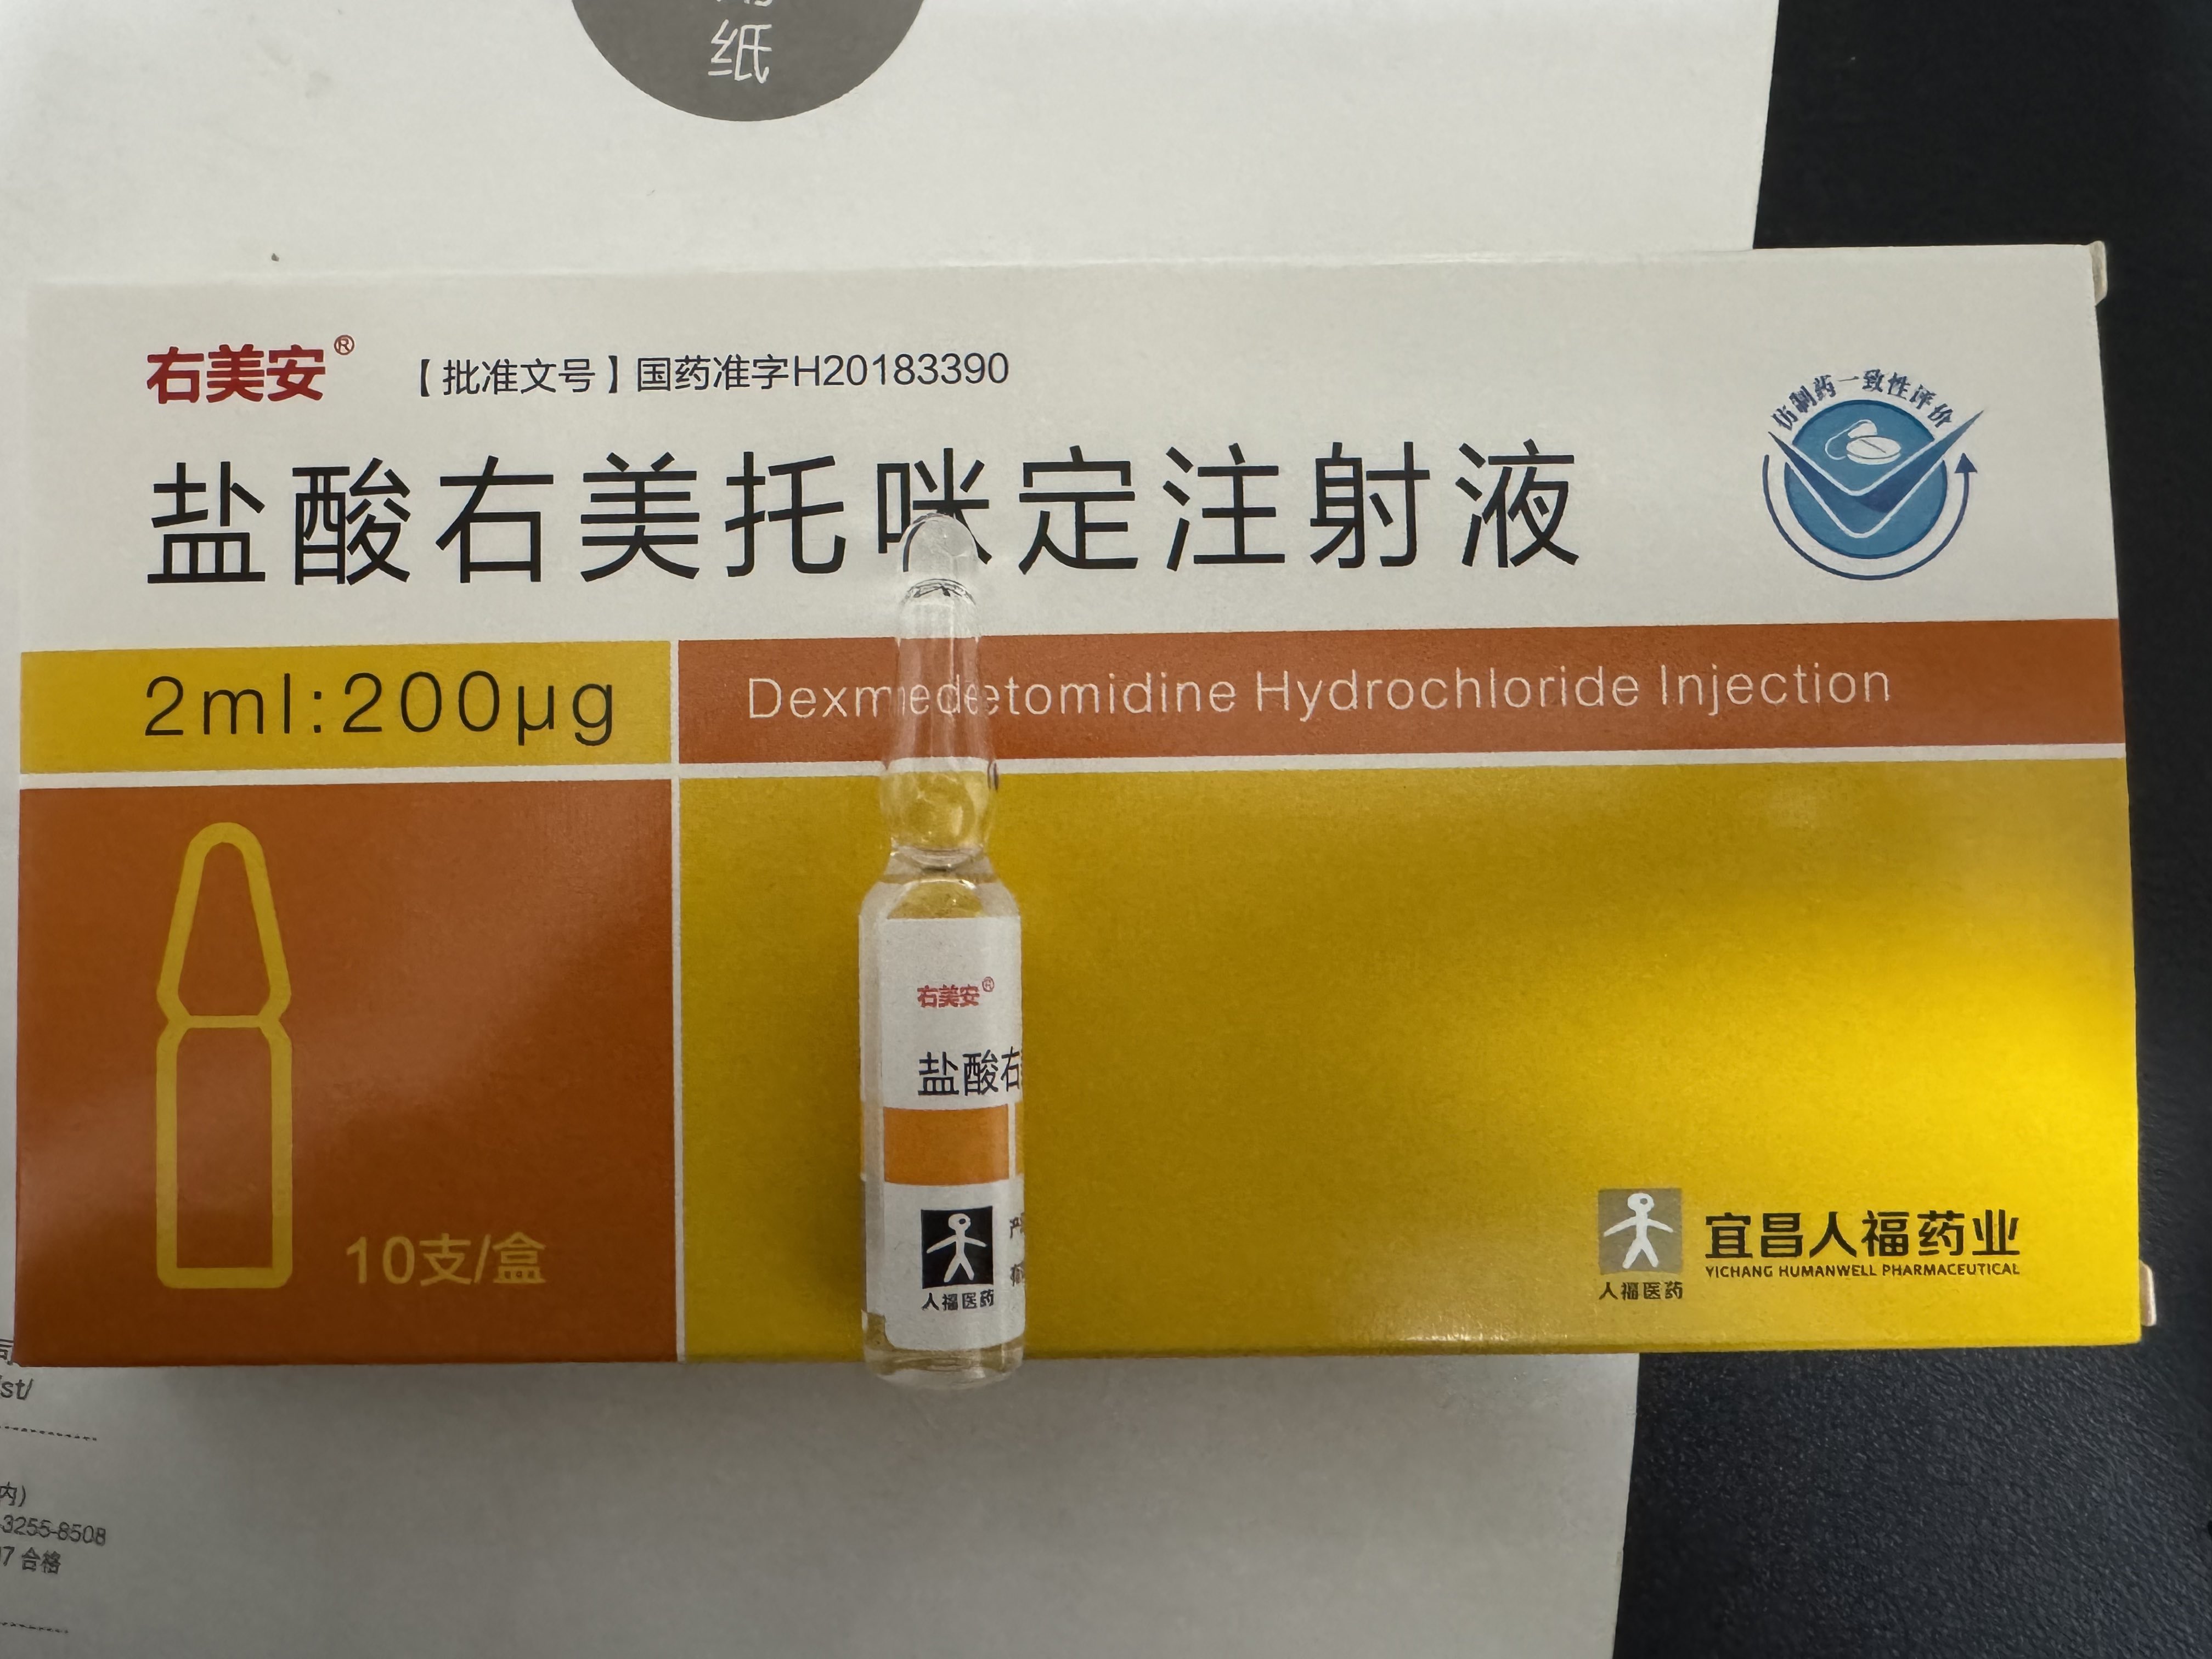

吃完唑吡坦会干一些难绷的事情,昨天睡不着疑似气急败坏了抽了0.5ml右美托咪定就是iv,还奇奇怪怪挑了个很痛的头静脉

后面不记得了,醒了灯开着的还以为是做梦,对着针孔一脸不可置信地整理记忆

你别说还扎得挺好的()按压时间估计也够,一点淤青也没有,不知道哪来的意志力 https://t.co/KxtfAUVSmb